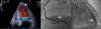

A 63‐year‐old man was admitted for non‐ST‐elevation myocardial infarction. Echocardiography showed preserved biventricular systolic function with apical hypokinesia. Apical 4‐chamber color Doppler view revealed abnormal diastolic flow, apparently intramyocardial (Figure 1A and Video 1). Coronary angiography revealed moderate (60%) coronary stenosis in the mid right coronary artery (Figure 1B), with a fractional flow reserve of 0.91, compatible with a functionally non‐significant lesion. Multiple small fistulae originating from both the right and left coronary arteries were observed, draining into the left ventricle (Figure 1B and C and Videos 2 and 3). Cardiac magnetic resonance imaging (MRI) provided further characterization of these fistulae, which were visible in T2‐weighted sequences in short axis view in the anterior and posterior interventricular grooves (Figure 2A). First‐pass myocardial rest perfusion imaging in two‐chamber view revealed epicardial hyperenhancement of the anterior wall simultaneous with aortic opacification (Figure 2B and Video 4), as well as earlier perfusion of the mid and apical anterior segments. There was subendocardial late gadolinium enhancement (LGE) in the apical inferior segment, compatible with non‐transmural myocardial infarction (Figure 2C). Dobutamine stress echocardiography under optimized therapy showed no inducible ischemia and the patient was discharged, and has remained stable ever since, now at two‐year follow‐up.

(A) Short‐axis T2‐weighted images with multiple unexpected small vascular structures in the anterior and posterior interventricular grooves; (B) first‐pass myocardial rest perfusion imaging in 2‐chamber view, showing epicardial hyperenhancement of the anterior wall simultaneous with aortic opacification (left) and earlier perfusion of the mid and apical anterior segments (right); (C) subendocardial late gadolinium enhancement in the apical inferior myocardial segment, in 4‐chamber and 2‐chamber views.